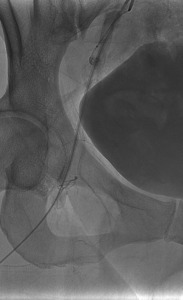

On POD #50 from the hysterectomy, the patient presented to the office with persistent vaginal cuff bleeding, less brisk than prior presentation. There were no sources of bleeding identified on exam. The patient then underwent a CT scan without any evidence of intraabdominal bleeding. Given persistent bleeding without a clearly identifiable source, the decision was made to proceed with bilateral embolization of the anterior divisions of the internal Iliac arteries. The embolization led to resolution of the vaginal cuff bleeding.

This patient’s localized labia minora pain was the result of nontarget labial embolization during bilateral internal Iliac artery embolization. The internal pudendal artery and uterine artery are adjacent to each other, branching off the anterior portion of the internal iliac artery. The internal pudendal artery supplies the labia minora. Most likely, injection of embolic material into the ligated uterine artery resulted in the reflux of particles into the right internal pudendal artery, producing ischemia in the branches supplying the labia.